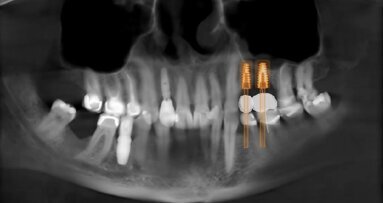

Dalla pianificazione computer assistita, alla chirurgia guidata, all’impronta ottica, al CAD/CAM: che le tecnologie digitali abbiano portato a ...

È un fatto che le tecnologie digitali si stanno diffondendo con estrema rapidità in medicina, e l’odontoiatria non fa eccezione. Anzi, ...